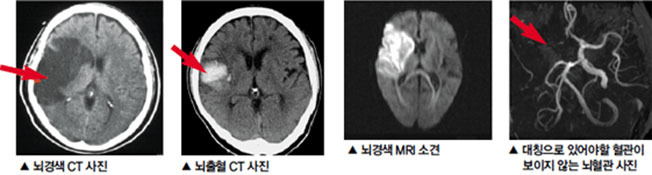

- ๋ณ์์ ๋์ฐฉํ๋ฉด CT ๋๋ MRI ๊ฒ์ฌ, ํ๊ด์ดฌ์ ๋ฑ์ด ์ด๋ฃจ์ด์ ธ ์์ธ ๊ท๋ช ๋ฐ ์น๋ฃ๊ณํ์ด ์ธ์์ง๋๋ค. PMC

๋๊ฒฝ์ ์ ์กฐ์ฆ์์ด ์์ฌ๋ ๋๋ MRI๋ CT ๊ฒ์ฌ๋ก ํ๊ด ์ํ๋ฅผ ์ ํํ ํ์ธํ๋ ๊ฒ์ด ์ค์ํฉ๋๋ค.

MRI๋ ํ๋ฅ ์ฐจ๋จ ๋ถ์๋ฅผ ์ธ๋ฐํ ๋ณผ ์ ์๊ณ , CT๋ ์ถํ ์ฌ๋ถ๋ฅผ ๋น ๋ฅด๊ฒ ํ์

ํ ์ ์์ต๋๋ค.